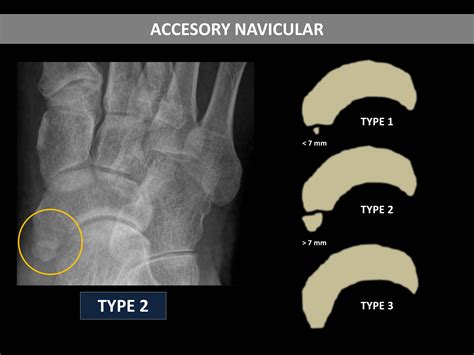

There are three main types of accessory navicular bone, classified based on their structure and connection to the navicular bone:

Type Description

Type I A small, round bone connected to the navicular bone by a fibrous or cartilaginous structure. This type is often asymptomatic.

Type II A larger, triangular bone connected to the navicular bone by a fibrous or cartilaginous structure. This type is more likely to cause symptoms.

Type III A large, triangular bone that is fused to the navicular bone. This type is often asymptomatic but can cause symptoms if there is inflammation or irritation.

• Imaging Tests: X-rays, MRI, or CT scans may be ordered to visualize the accessory navicular bone and assess its structure and connection to the navicular bone.

These diagnostic tools help determine the type of accessory navicular bone and the extent of any associated symptoms.